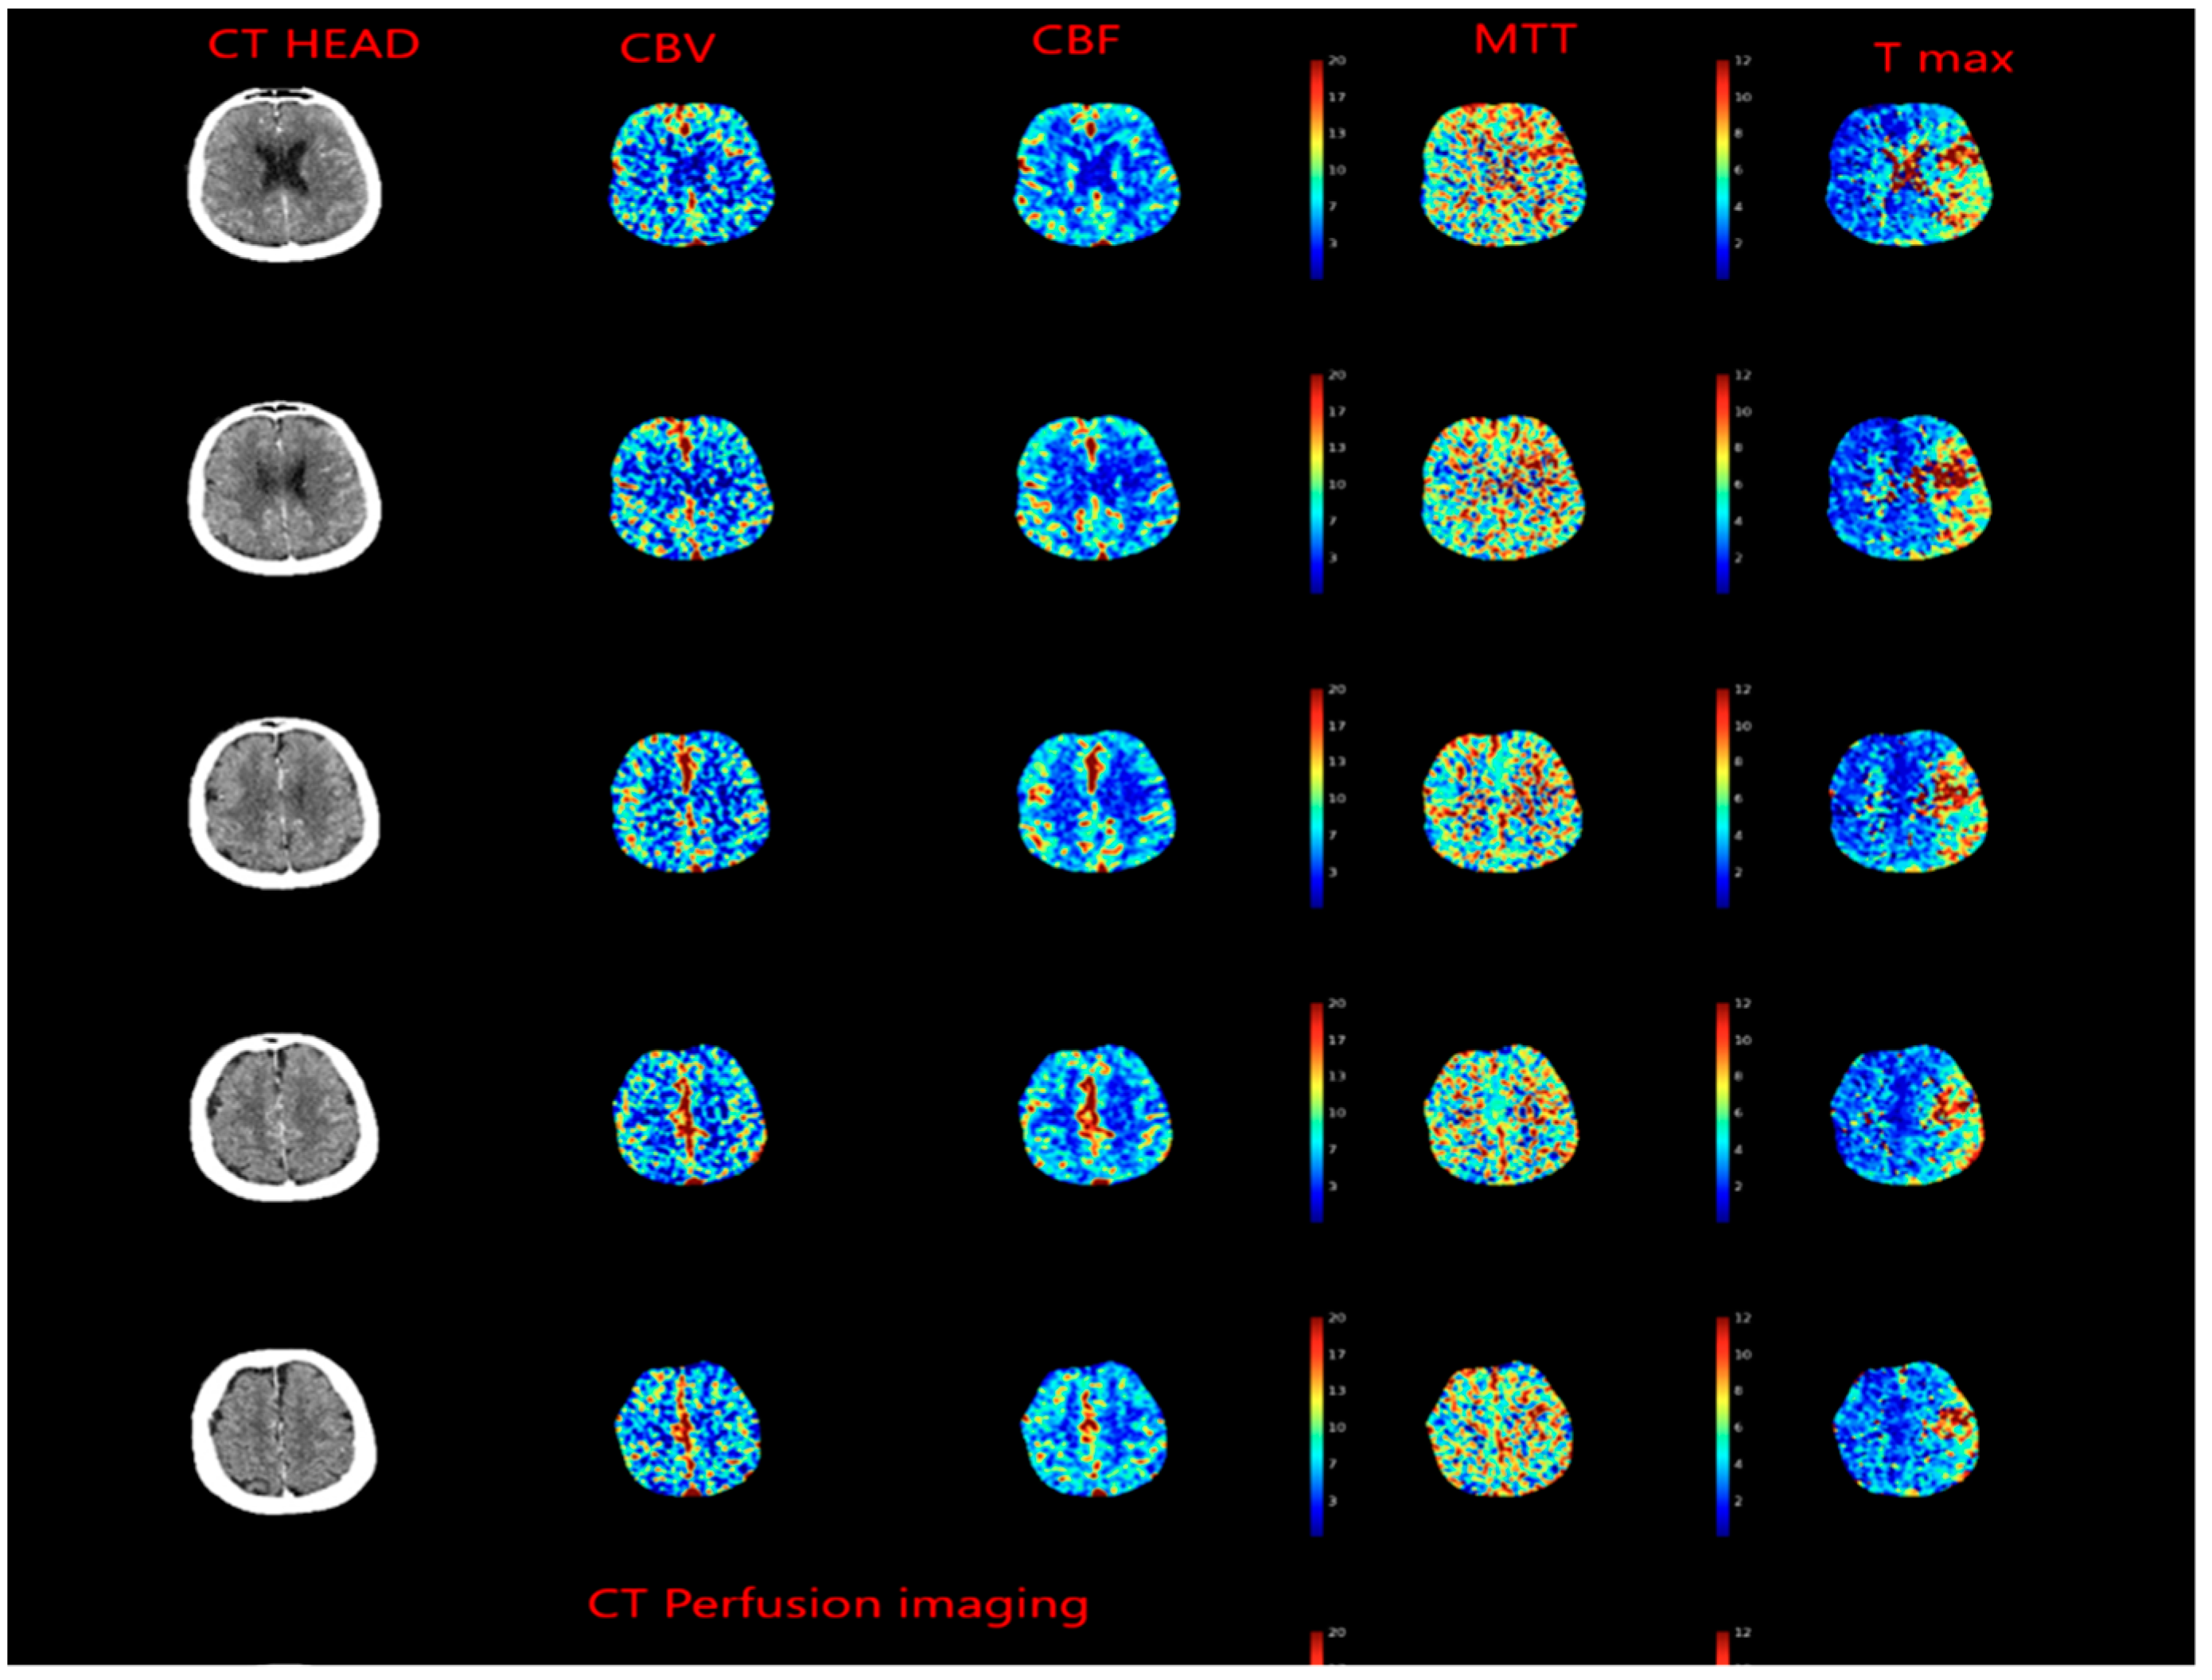

2.5. Evolution of the Concept of the Tissue Window and Late Window Trials

- Campbell, B.C.; Mitchell, P.J.; Kleinig, T.J.; Dewey, H.M.; Churilov, L.; Yassi, N.; Yan, B.; Dowling, R.J.; Parsons, M.W.; Oxley, T.J.; et al. Endovascular therapy for ischemic stroke with perfusion-imaging selection. N. Engl. J. Med. 2015, 372, 1009–1018. [Google Scholar] [CrossRef] [Green Version]

- Albers, G.W.; Marks, M.P.; Kemp, S.; Christensen, S.; Tsai, J.P.; Ortega-Gutierrez, S.; McTaggart, R.A.; Torbey, M.T.; Kim-Tenser, M.; Leslie-Mazwi, T.; et al. Thrombectomy for Stroke at 6 to 16 Hours with Selection by Perfusion Imaging. N. Engl. J. Med. 2018, 378, 708–718. [Google Scholar] [CrossRef]